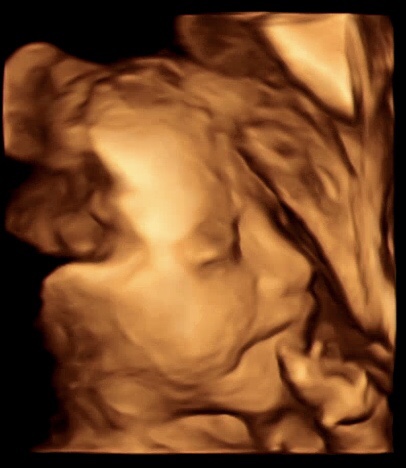

삐약이 탄생 ?

지난 11월11일 어느때와 같이 막달검사를 하러 산부인과로 남편과 갔다. 근데 이게 뭐람 양수가 부족하다고...

최후의만찬

오늘도 어김없이 남편과 산부인과가서 태동검사를 진행하고 초음파를 확인했다. 이게 무슨일..? 양수가 없...